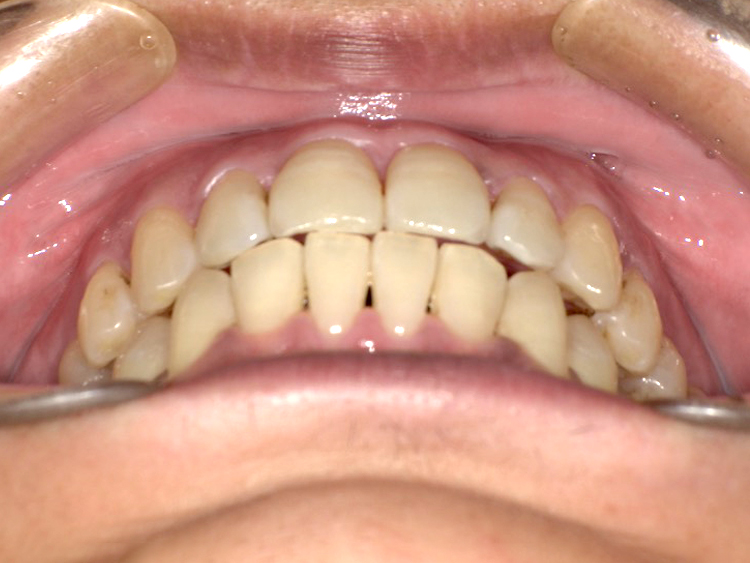

症例5

Before

After

| 主訴 | 上下3-3の並びが気になる |

|---|---|

| 年齢 | --- |

| 治療 期間 |

約1年 |

| 治療 内容 |

インビザライン5-5 |

| 治療費 | ¥517,000(税込)/調整料含む |

| 治療のリスク | 奥歯を動かさないので、前に出して並べていく。 歯と歯が移動するスペースを作るので、知覚過敏の症状がまれにでる。 歯を動かすことで、歯茎が下がるリスクある。 矯正終了後は、リテーナーを使用し、後戻りを防ぐ必要がある。 |